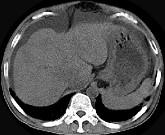

男,44岁,有乙肝病史,现腹胀,右上腹痛,消化不良,消瘦、乏力、贫血、黄疸,血清转氨酶升高,清蛋白/球蛋白比值倒置。CT、MRI检查如下图,最准确的诊断是...

问题 男,44岁,有乙肝病史,现腹胀,右上腹痛,消化不良,消瘦、乏力、贫血、黄疸,血清转氨酶升高,清蛋白/球蛋白比值倒置。CT、MRI检查如下图,最准确的诊断是 ( )

选项 A.肝硬化并腹水 B.肝硬化并腹水、再生结节 C.肝硬化腹水、肝癌 D.肝硬化并再生结节 E.肝硬化并腹水、脂肪肝

答案 B